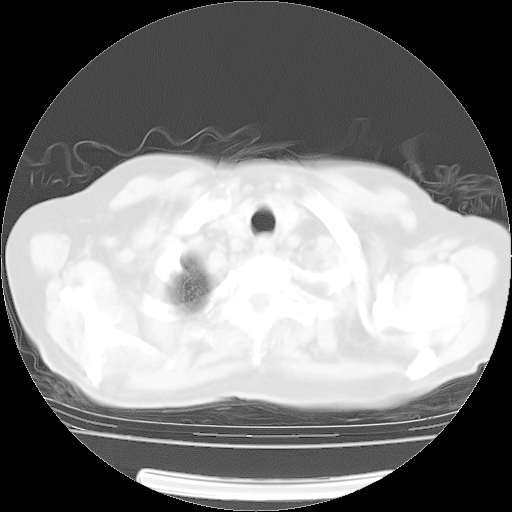

肺部CT平扫未见异常。